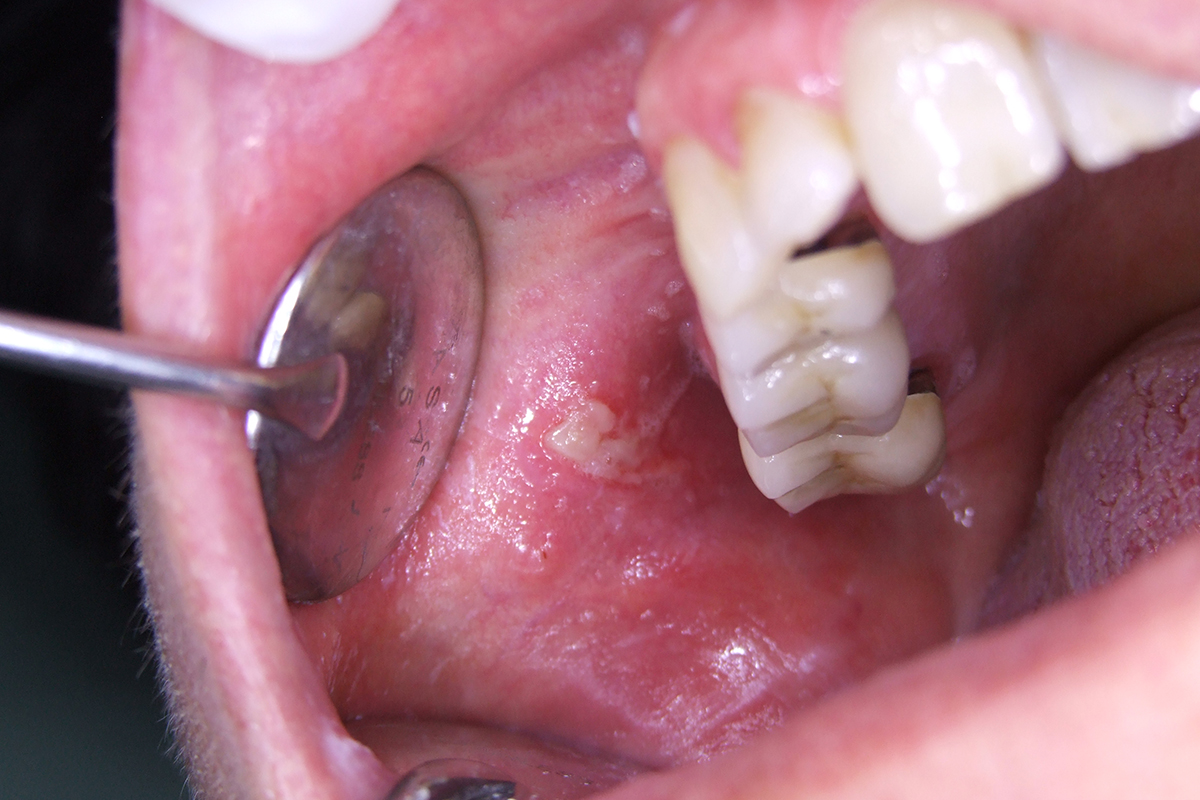

TRAITEMENT DE L’APHTE BUCCAL

L’aphte est une lésion ronde, blanche ou grisâtre, entourée d’un halo rougeâtre, dont la taille peut varier de un à dix millimètres. Le traitement au laser permet de réduire considérablement l’inflammation et la douleur, ce qui accélère le processus de guérison, qui intervient au bout de 2 à 4 jours.